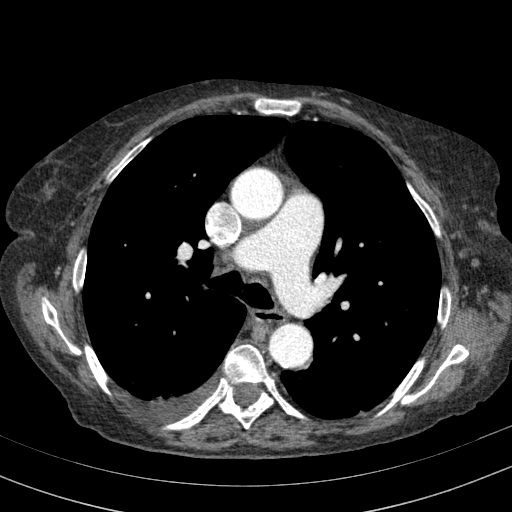

Targeted Slice 70 - Mediastinum Window Analysis (Generated vs Real Venous)

0.625

Mediastinum SSIM

56.4

Mediastinum RMSE

25.0

Mediastinum MAE

Average Mediastinum Window Metrics Across All Slices (153 slices) - Generated vs Real Venous

0.556

Mediastinum SSIM (Avg)

58.5

Mediastinum RMSE (Avg)

29.2

Mediastinum MAE (Avg)

Mediastinum window (WL 40, WW 400 β†’ Low βˆ’160, High +240)